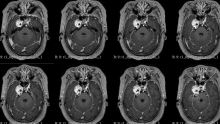

“朝花夕拾”潍人医脑肿瘤之经典病例篇——神经内镜下经鼻经翼突入路切除麦氏囊三叉神经鞘瘤1例

脑肿瘤-神经鞘瘤

潍坊市人民医院神经外五科(神经肿瘤病区) 关注

潍坊市人民医院前天10:23 646阅读 1评论 3点赞 -